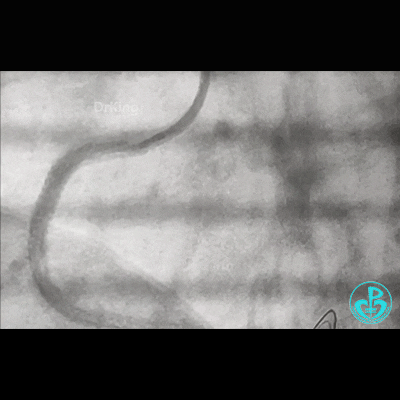

冠脉造影

右锁骨下动脉迂曲打圈,影像如下:

病变简单吧!